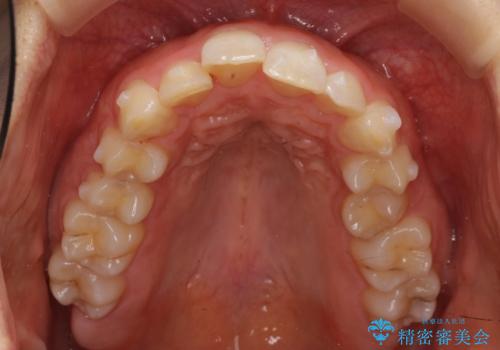

- 前歯のがたがたと出っ歯を主訴に来院。

CTを撮影したところ、臼歯部の頬側の骨の厚みが非常に大きく、通常では考えられない量の歯列の拡大が可能でした。

今回は健康を損なわずに非抜歯で治療が可能でしたが、

歯ぐきや骨の厚みが薄い他の患者さんでは難しいです。

左上5は180度捻転していましたので、そのまま並べています。

遠心移動などは行わず、IPRと拡大のみで治療を行いました。

一般的に非抜歯矯正を無理に行うと、口元がモッコリ出てしまうことがあります。しかし、今回は前歯を前に出さないような設定にしており、口元が出ることもありませんでした。